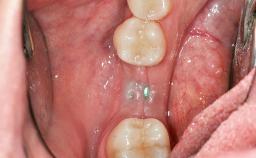

# of Teeth 1

# of Implants 1

Type of Implants One-Piece